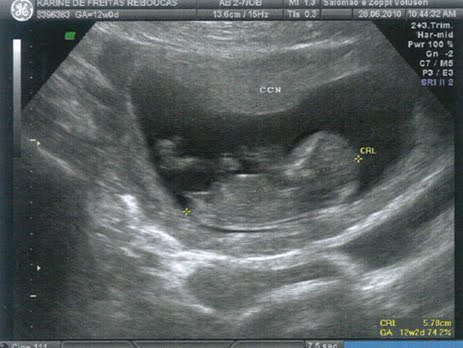

Ontem fui ao médico com meu pai e minha mãe. Fizemos a ultrassonografia e o médico disse que está tudo bem comigo.

Estou grande, forte e saudável, com 32 cm de tamanho e pesando 800 gramas! Estou tão bonita, que um paparazzo tirou uma foto minha para publicar na internet. Olha ela aí: